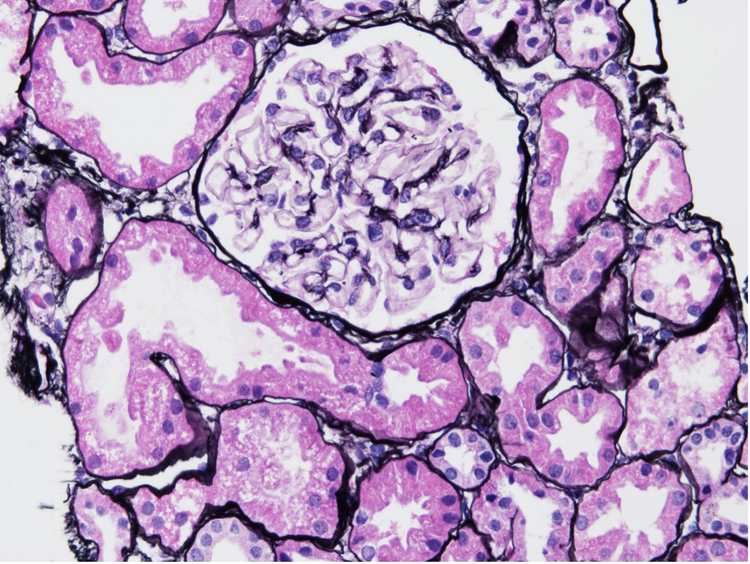

For example, Figure 1 shows kidney samples of LN class 1 early-stage patients, with no significant glomerular changes compared with healthy subjects. 2

Figure 1. LN class 1 kidney sample biopsy sample, stained with Jonas silver stain.